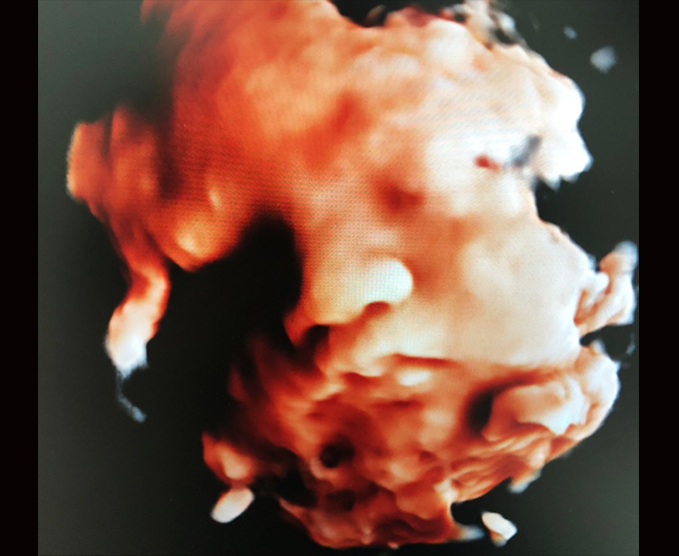

El ultrasonido obstétrico utiliza ondas sonoras para producir imágenes de un bebé (embrión o feto) que está dentro de una mujer embarazada, como así también del útero y los ovarios de la madre. No utiliza radiación ionizante, no tiene efectos nocivos conocidos, y es el método preferido para la vigilancia de las mujeres embarazadas y sus bebés que aún no han nacido.